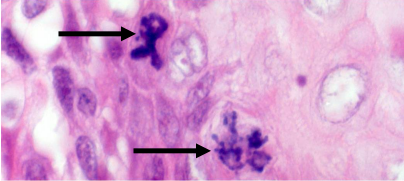

问题4、图2箭头所指的是什么病理学结构?

图2:高倍镜下的一个视野